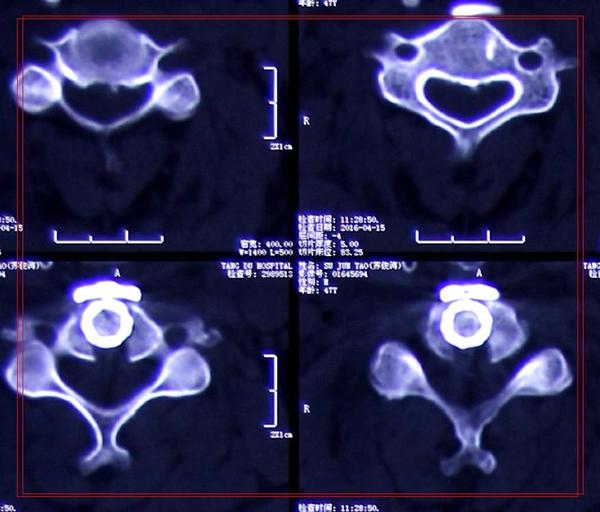

治疗:显微镜下单节段颈椎间盘切除植骨融合内固定术

术后:术后2天,患者四肢麻木、颈肩部不适症状即缓解并可下床活动。同时,心慌胸闷症状完全缓解。

影像学资料